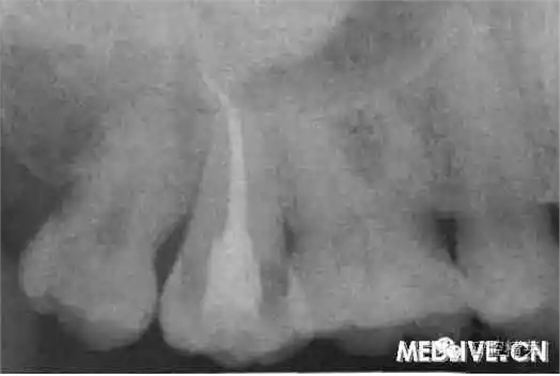

7⊥頜面中央窩見開髓洞型,叩痛(++),無松動。X線片示7⊥牙根融合為一彎曲單根,根管粗大,根尖1/3偏向遠中,無充填物,未見髓室底(圖1上)。錐形束C’r檢查示:根管橫斷面僅見一個根管口略呈啞鈴形,頰舌向管徑粗大,中下1,3存在牙本質(zhì)島,根尖1,3明顯彎曲偏向遠中,彎曲角度為34.30(圖2上)。

圖1上:初診;下:根管充填后

上:初診:下:根管充填后。